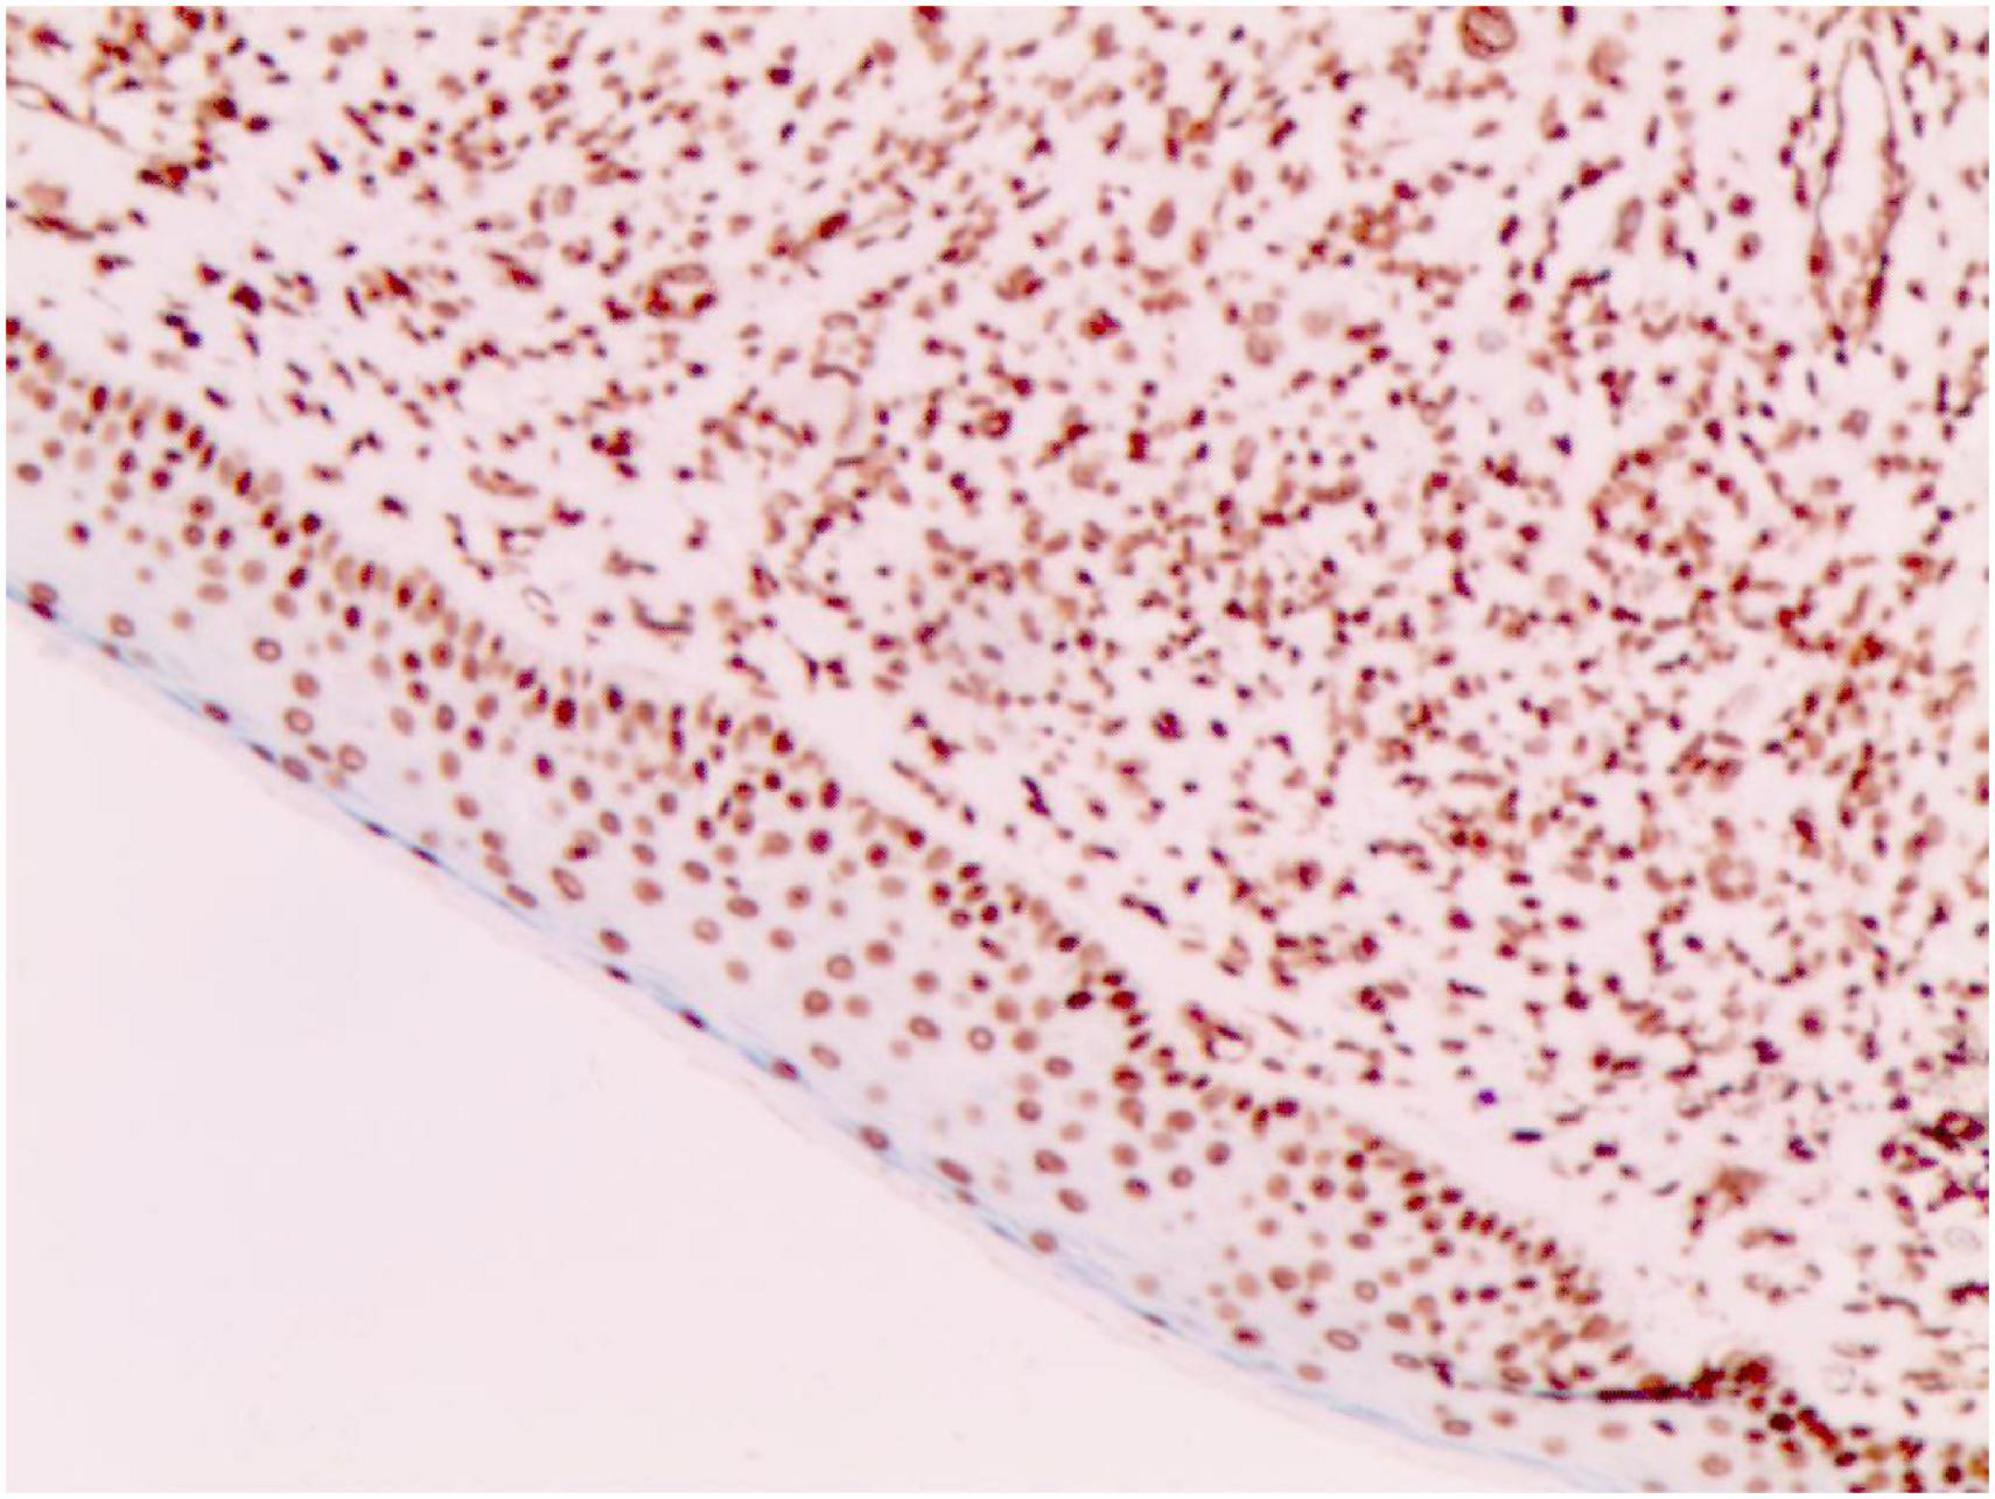

FIGURE 4

S-100 (+) (Immunohistochemical staining, × 200).

No abnormalities were found upon routine blood and urine tests, coagulation function test and syphilis/HIV screening. Chest X-ray and abdominal B-ultrasound also revealed no abnormalities. Cutaneous histopathology: epidermal processes disappeared, and the dermis was diffusely infiltrated by substantial tumor cells that were in the nested or clumpy form. These polygonal tumor cells were round or oval, which had abundant cytoplasm filled with eosinophilic granules, and were stained pale pink. The cellular nuclei were small, hyperchromatic and centered, with few mitotic figures, and multiple nuclei were observed in some tumor cells. Immunohistochemistry: S-100 (+), CD56 (−), NSE (−), vimentin (+), CD68 (+), Ki-67 (+), cell proportion: 5%, p53 (−), SAM (+−). CK (−), calponin (−), CD163 (−), desmin (−), CD34 (−), CD45 (−), CD30 (−), SMA (1A4) (−), ALK (−), HMB45 (−), melan-A (−).

2.3.3 The immunohistochemical results

Diagnosis of GCTs is based primarily on the histopathological examination. Regarding the histopathological features of GCTs, the lesions are located mainly in the dermal, subcutaneous or submucosal tissue, and the tumor cells mostly exhibit banded or nested growth. The tumor cells are large, polygonal and filled with fine eosinophilic granules in the cytoplasm. The cellular nuclei are small and centered, which are either round or oval. Common immunohistochemical markers: S-100 protein (+), NSE (+), CD68 (+), CK (−), SMA (−), GFAP (−), etc.